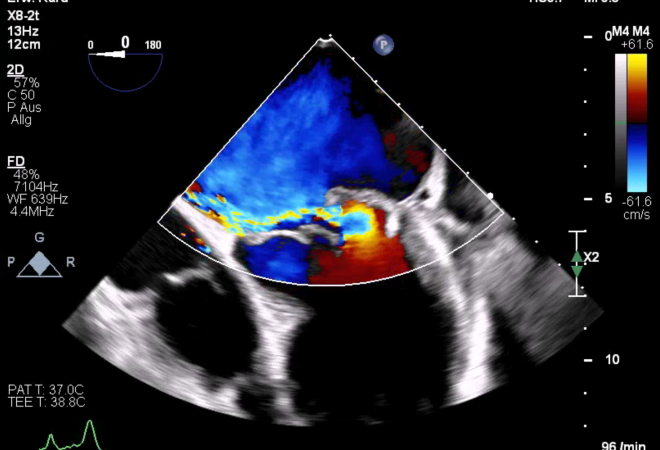

Die Echokardiografie ist mittlerweile in der Anästhesie und Intensivmedizin ein etabliertes Verfahren im klinischen Alltag. Mit dem Angebot dieses Grundkurses möchten wir einen entspannten Einstieg in die Welt des Herzultraschalls bieten und Berührungsängste abbauen. Wir wollen wir Ihnen die Ultraschallanwendung und ihre Möglichkeiten näherbringen sowie Sie auf den klinischen Einsatz der Echokardiografie in den verschiedenen Einsatzbereichen vorbereiten. Mit einem hohen Praxisanteil werden Ihnen relevante theoretische Grundkenntnisse der transösophagealen Echokardiografie vermittelt. Neben Impulsvorträgen möchten wir viel Gelegenheit zum Umsetzen des Gehörten in die Praxis geben. Dies realisieren wir in Kleingruppen mittels praktischen Übungen, unter anderem auch mittels Ultraschallsimulatoren oder bei Demonstrationen auf der Intensivstation oder im Operationssaal. Für ein optimales Lernsetting bietet unser Kurs ein Betreuungsverhältnis von 1:4.

13:00 – 13:15 Einführung in die Doppler-Sonographie (PW, CW, Farbdoppler) Pop

13:15 – 13:45 Beurteilung der Aortenklappe Pop

13:45 – 14:15 Beurteilung der Mitralklappe Arends

16:00 – 16:30 Beurteilung von Trikuspidal- und Pulmonalklappe Kholaif

16:30 – 17:00 Basics & Beurteilung von Klappenprothesen und -rekonstruktionen Börgermann